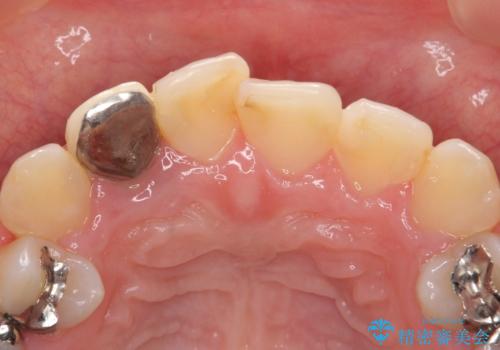

- 右上2番目の歯の被せ物と歯茎の間の継ぎ目が気になるといらっしゃった方の症例です。

再根管治療は希望されなかったため、クラウン除去後、オールセラミッククラウン(スペシャル)による補綴を行いました。

- オールセラミッククラウン(スペシャル)…¥130,000、仮歯…¥10,000、ファイバーコア…¥20,000費用は治療当時の料金となります